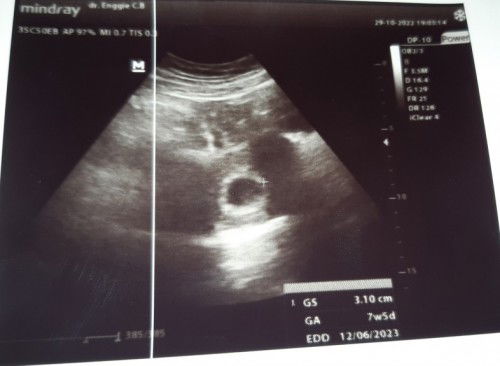

Hasil USG 7w 5d

Hasil USG pertama usia 5w blm kelihatan apa2, 2mingguan balik USG lagi alhamdulillah sudah kelihatan kantung janinnya. Meskipun hpht 8w 3d tpi USG nya 7w 5d selang hampir 1minggu it's okay yg penting bidan bilang sehat dan normal. Minta doanya ya bund smoga sehat dan lancar sampai persalinan. Saya doakan juga smoga ibund2 kehamilannya sehat dan normal, dilancarkan dan dimudahkan sampai persalinan 🤲🥰

Waktunya USG pertama usia 5w belum kelihatan apa2, Alhamdulillah USG kedua sdah kelihatan kantongnya. Meskipun hpht 8w 3d tapi USG 7w 5d tp i'ts okay yang penting bidan bilang sehat dan normal udah lega rasanya. Semoga ibun2 disini kehamilannya sehat dan normal juga, slalu diberi kelancaran sampai lahiran 😊🥰